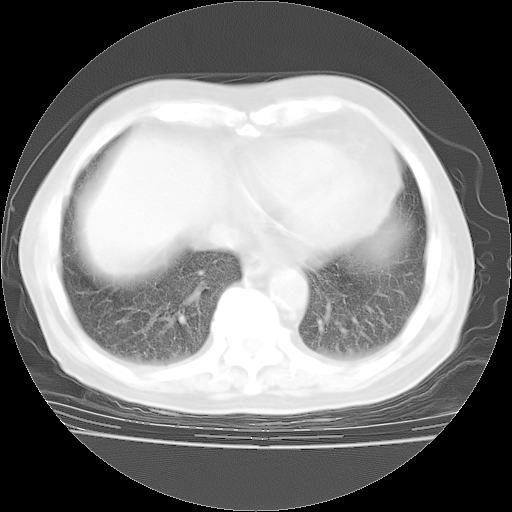

4月28日肺部CT——再次出现类似去年5月9日——透光度降低,“间质性”改变。

4月28日肺部CT——再次出现类似去年5月9日——磨玻璃样、间有“粟粒样”改变。

个人阅读4.14日肺部CT平扫:纵隔窗无异常,但肺窗示:双下肺内、后基底段有片絮状侵润影,部位以后基底段为著,以间质改变为主,呈急性肺泡炎征像,和首次住院影像学有相似之处。仅是个人读片,明日请相关专家再读片哈。其它建议同上。

1、108#的是4月14日的胸部CT(发此贴时还没看着28日的CT)。14日的胸部CT其实已经出现改变(如108#所述),个人认为28日的胸部CT除纵膈窗疑似有双侧胸膜增厚或少量胸积液(可行胸部B超明确)外,与4月14日对照病变有所加重;2、已经给予“异烟肼、利福平、乙胺丁醇”抗痨治疗?如果是,甲强龙80mg可缓慢减量;如果环磷酰胺已停用,暂不使用;3、中性粒细胞92%,明显升高,目前体温情况?注意合并细菌感染可能,使用左氧氟沙星情况下,是否联用B-内酰胺类抗菌药物?另外是查免疫全套非风湿全套。

今请临免主任会诊后认为:4月14日胸部CT已有双下肺间质性改变。患者病情复发多系激素减量过快不正规所致。目前甲强龙80mg/日,一周后酌情开始减量,不易过快。环磷酰胺若已停用,暂不使用。他同意目前抗菌药物使用,但应考虑是否加用B-内酰胺类抗菌药物(中性细胞明显增高);2、结核复发目前依据不足;3、若免疫全套各项指标正常,考虑多系特发性肺间质炎可能大。4、加强支持,并注意保护胃黏膜。

今上午去请教了临免、呼吸主任:1、介绍病史和阅读系列胸部CT一致认为:患者肺结核不考虑,仍为肺间质纤维化,目前处于急性肺泡炎阶段。2、若仍发热,可将甲强龙增至:80mg Bid静滴,同时鉴于中性增高,合并细菌感染可能,继续左氧氟沙星治疗,再联用B-内酰胺抗菌药物,如头孢哌酮--舒巴坦;3、停用抗痨药;4、目前甲强龙每日剂量160mg ,体温正常后再酌情减量;目前暂不用免疫抑制剂;4、不建议使用免疫增强剂等;5、加强支持治疗,鼓励患者进食;5、注意随访肝、肾功及血常规情况;6、因患者目前激素用量较大,加用胃黏膜保护剂,防止消化道出血可能。